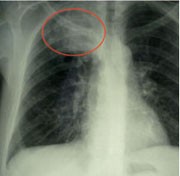

Abb. 2 Lokal weit fortgeschrittenes Bronchialkarzinom bei HIV pos. Patienten, Stadium IIIA

Therapeutisch gilt wie bei HIV-negativen Patienten, dass nur jene Patienten eine Überlebenschance haben, deren BC früh erkannt und diagnostiziert wird. Die Symptome sind unspezifisch, und wenn sie auffallen, ist es meistens zu spät. Bei HIV-Patienten wird die Diagnose leider nur selten rechtzeitig gestellt. In unserer eigenen Kohorte von 72 Fällen aus den Jahren 2000-2010 waren nur 34% in den zumindest theoretisch noch operablen UICC-Stadien I bis IIIa (Hoffmann 2011). Patienten in frühen Tumor-Stadien sollten möglichst in kurativer Intention operiert werden, Chemotherapien gewähren nur einen kurzen Aufschub um einige Monate. Die mediane Überlebenszeit lagen in früheren Kohorten bei 4-8 Monaten (Tirelli 2000, Spano 2004, Powles 2003, Cadranel 2006, Lavolé 2006+2009), in unserer eigenen Auswertung bei 12 Monaten – die Höhe der CD4-Zellen und limitierte Stadien waren dabei wesentliche Einflussfaktoren (Hoffmann 2011). Nur in sehr frühen Stadien, vor allem bei Stadium I, ist auch ein Langzeit-Überleben von mehr als zwei Jahren möglich.